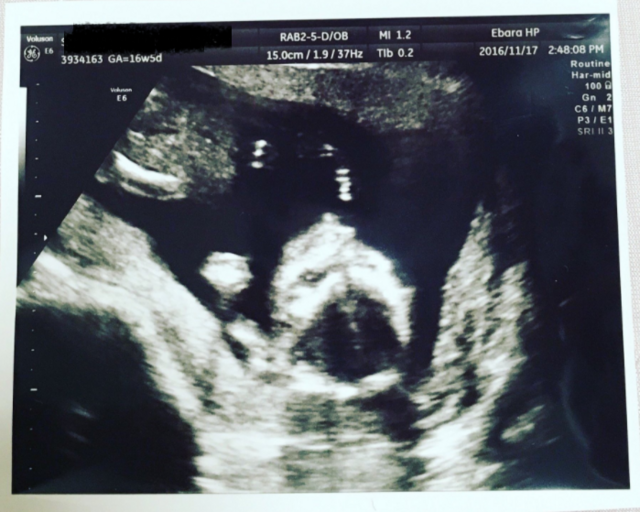

16週6日(16w6d・男の子)|keiichi さん(32歳)

エコー写真撮影時のエピソード:

待ちに待った安定期。前回の診察から間があいたのでドキドキしながらエコーに臨んだら、背骨がくっきり見えました!たまたま母と一緒に診察に行った日で、初孫のエコーに母がはしゃいでいたのを良く覚えています。帰ってから写真を見せたら、パパも大喜びしていました。